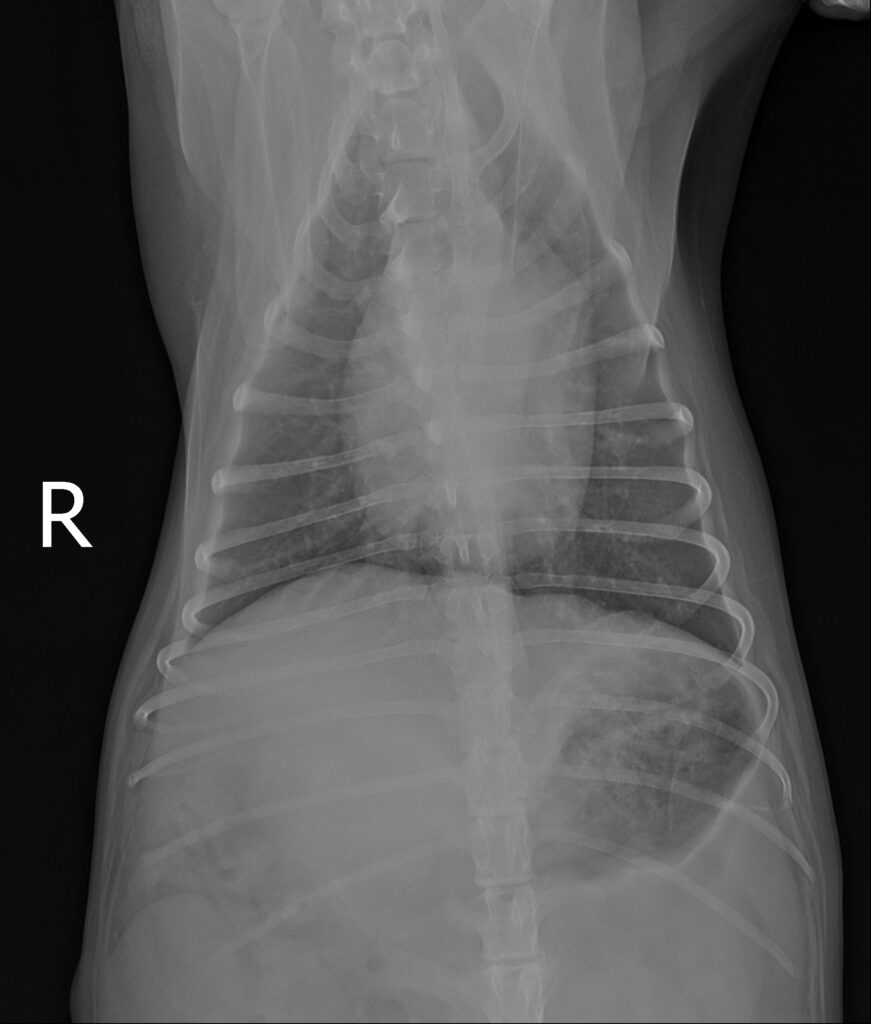

흉부 방사선 검사 결과 / 출처:24시온숲동물의료센터

복부초음파·방사선검사 결과

- 내원 당시 시행한 복부 초음파 및 방사선 검사에서 정상적으로는 4mm 정도 두께인 자궁이 약 4cm까지 심하게 확장되어 있는 모습이 확인되었습니다. 내부에는 고름으로 추정되는 내용물이 가득 차 있었으며, 이는 전형적인 자궁축농증의 소견에 해당합니다.